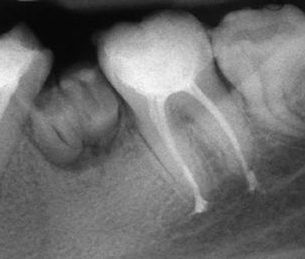

Запълване с препресване

Ендодонтия